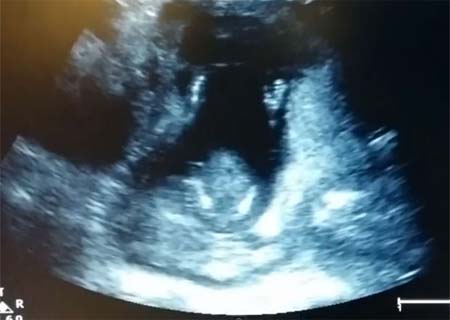

Foto: reprodução/Youtube

Um feto, de 14 semanas, acompanha a cantoria dos pais e bate palmas durante a ultrassonografia.

E ele bate no ritmo da música cantada pelos pais.

O mais engraçado é que a canção diz “se você está feliz e você sabe, bata palmas’… aí o bebezinho bate!!! (assista abaixo)

Para surpresa de todos, incluindo o marido, o bebê aparece batendo palmas em 3 ocasiões, enquanto seus pais cantam a música If You’re Happy and You Know It!